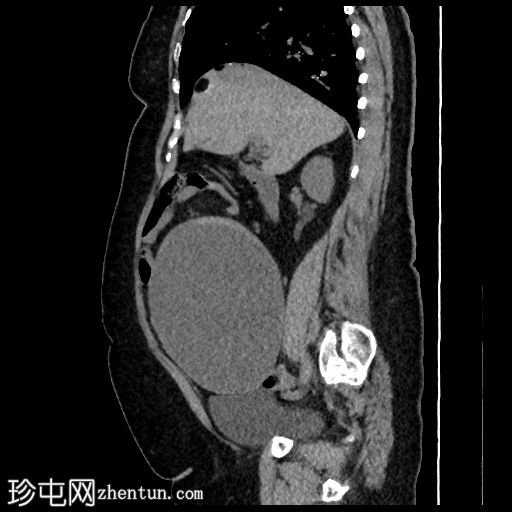

2.jpg

矢状位

平扫

腹盆腔可见较大的规则、薄壁病变,主要为液体,内部可见含脂肪的小叶和边缘钙化,符合卵巢畸胎瘤的影像学表现。